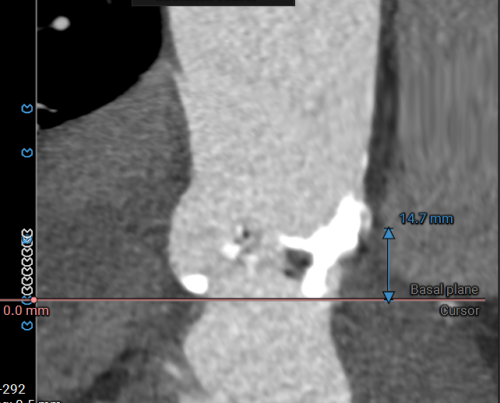

左冠开口高度14.7mm

左冠开口高度12.1mm